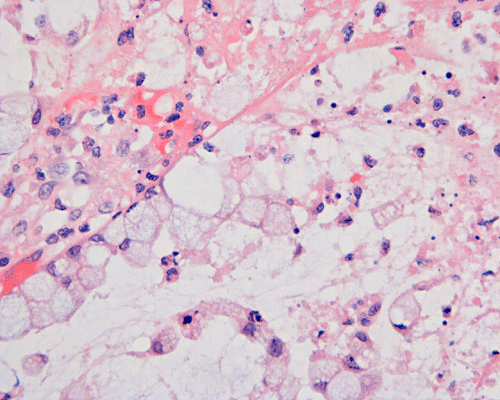

Histopathology: On scanning magnification, the mucosa has a sandwich like structure (Panel A). At the bottom is a layer of partially destroyed glands with a middle layer of mucoid material and topped by a layer of inflammatory exudate (Ž in Panel A). In some areas, the inflammatory exudate takes the shape of a mushroom or volcano (Panel B). The submucosa is edematous but lacks significant inflammatory cell infiltration. The top layer of inflammatory exudate is composed exclusively of degenerated polymorphonuclear leukocytes (Panel C and D). At the base of the mucosa, the outline of the normal glandular architecture is maintained but there is intense infiltration by polymorphonuclear leukocytes in the lamina propria (Panel E and F). On high-magnification, the crypts are filled by signet ring cells. In severely inflammed areas, there are some single singnet ring cells in the lamina propria (Panel G). In the deeper part of the mucosa where inflammation is not as intense, the boundary between the crypts and the lamina is respected by the signet cells (Panel H). In the more superficial part of the mucosa, the glandular architecture is disrupted (Panel I). Sporadic signet ring cells are also found in mucosa that are relatively unaffected (Panel J).

While there are general features which can be used to differentiate benign signet-ring cell changes from signet-ring cell carcinoma on hematoxylin and eosin stained sections, well-differentiated signet-ring cell carcinoma may be more difficult to exclude. General features which can be used to define benign signet-ring cell changes are the absence of infiltration of signet ring cells into the lamina propria and bland cytologic features. Extensive signet ring cells may be noted within the crypts and the inflammatory exudates. 6, 9. Infiltrating signet ring cells in a location remote from the main bulk of signet ring cells raises a strong suspicion of signet ring cell carcinoma. Immunohistochemistry for cytokeratin and, to a less extent, mucicarmine stain are helpful in demonstrating these clusters.